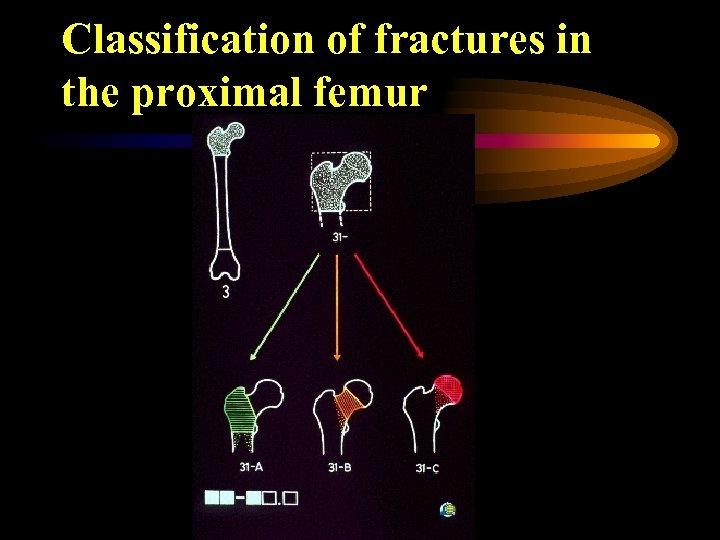

Classification of fractures in the proximal femur

Classification of fractures in the proximal femur